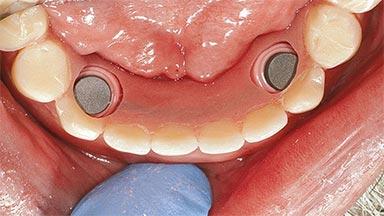

# of Implants 2

Type of Implants One-Piece

Attachment One-Piece

Defining Characteristics Fully edentulous lower jaw to be rehabilitated with an implant-borne removable overdenture

Loading Protocol Conventional/early